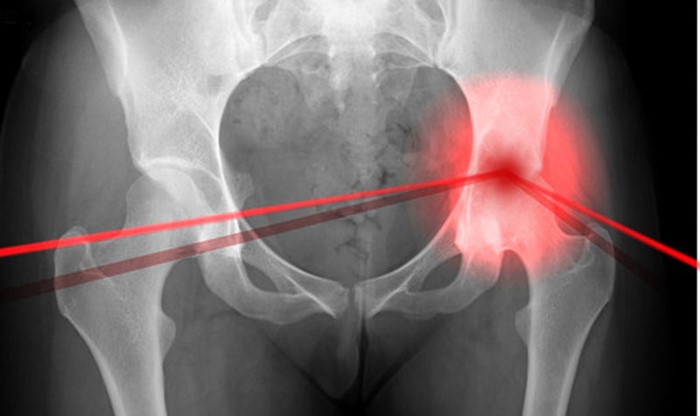

Артрит тазобедренного сустава — воспалительное заболевание, которое ухудшает качество жизни, вызывая боль и ограничивая подвижность. В статье рассмотрим основные симптомы артрита и эффективные методы лечения. Знание признаков и терапевтических подходов поможет читателям вовремя обратиться за медицинской помощью и выбрать оптимальные стратегии для управления заболеванием, что способствует улучшению состояния и восстановлению активности.

Течение патологии зависит от того, насколько далеко зашел воспалительный процесс. Для выявления развития артрита ТБС, врачи выделяют четыре степени, каждая из которых обладает своими характеристиками. Определить стадию артрита можно только при помощи рентгена.

- рентгенография пораженных суставов;